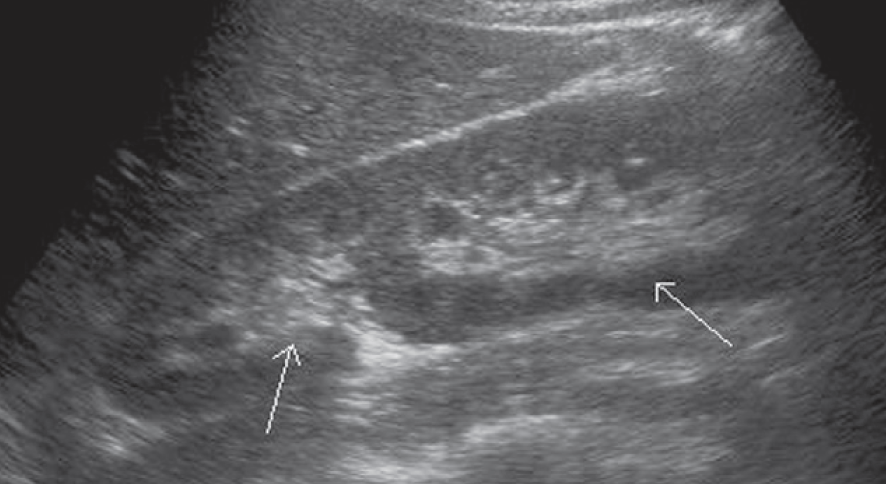

2-Kidney hump

تسمى أيضا Dromedary hump وهي مثل البروز في شكل parenchyma الكلية كسنام الجمل. سماكتها يجب أن تتناسق مع بقية parenchyma المحيطة بدون بروز. هي شائعة تحديدا في الكلية اليسرى وذلك لأن التغير يحدث في مرحلة تطور الجنين وضغط الطحال على الكلية.

في هذه الحالات يجب التأكد من السماكة (متناسقة) و echogenicity (غير مختلفة) و colour Doppler (طبيعية).